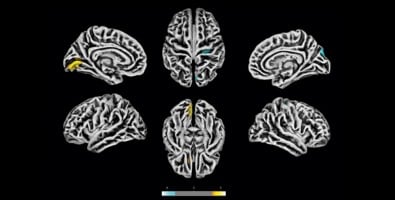

Pela análise dos exames de ressonância magnética foi possível perceber que algumas regiões do córtex dos voluntários tinham espessura menor do que a média observada nos controles, enquanto outras apresentavam aumento de tamanho – o que, segundo os autores, poderia indicar algum grau de edema.

“Observamos atrofia em áreas relacionadas, por exemplo, com a ansiedade – um dos sintomas mais frequentes no grupo estudado. Considerando que a prevalência média de transtornos de ansiedade na população brasileira é de 9%, os 28% que encontramos é um número elevado e alarmante. Não esperávamos esses resultados em pacientes que tiveram doença leve”, afirma Yasuda.